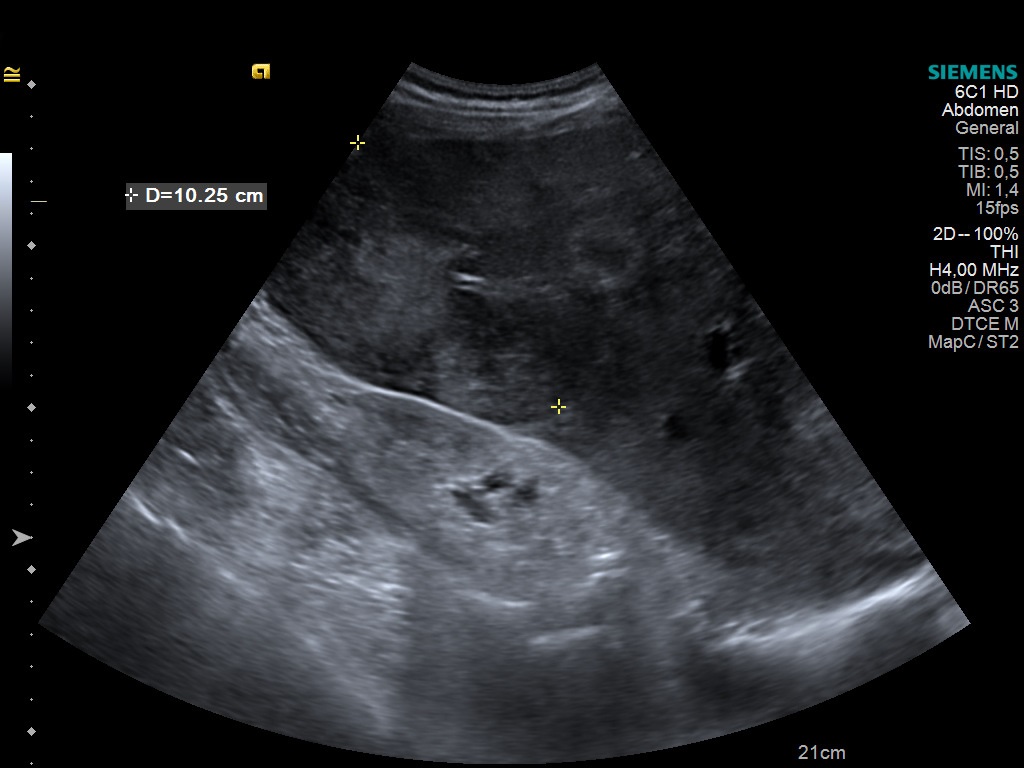

A 63 year old male with right upper quadrant pain and jaundice, with a history of chronic hepatitis B viral infection has the following US image. What is your diagnosis?

Case courtesy of Prof Adrian Saftoiu